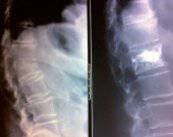

Cada vez es más común ver a niños que pasan horas sentados, en posturas poco saludables, con escasa actividad física y mínima interacción social en espacios al aire libre. Esta falta de movimiento impacta directamente en su desarrollo musculoesquelético, dando lugar a problemas que antes eran inusuales a tan temprana edad.